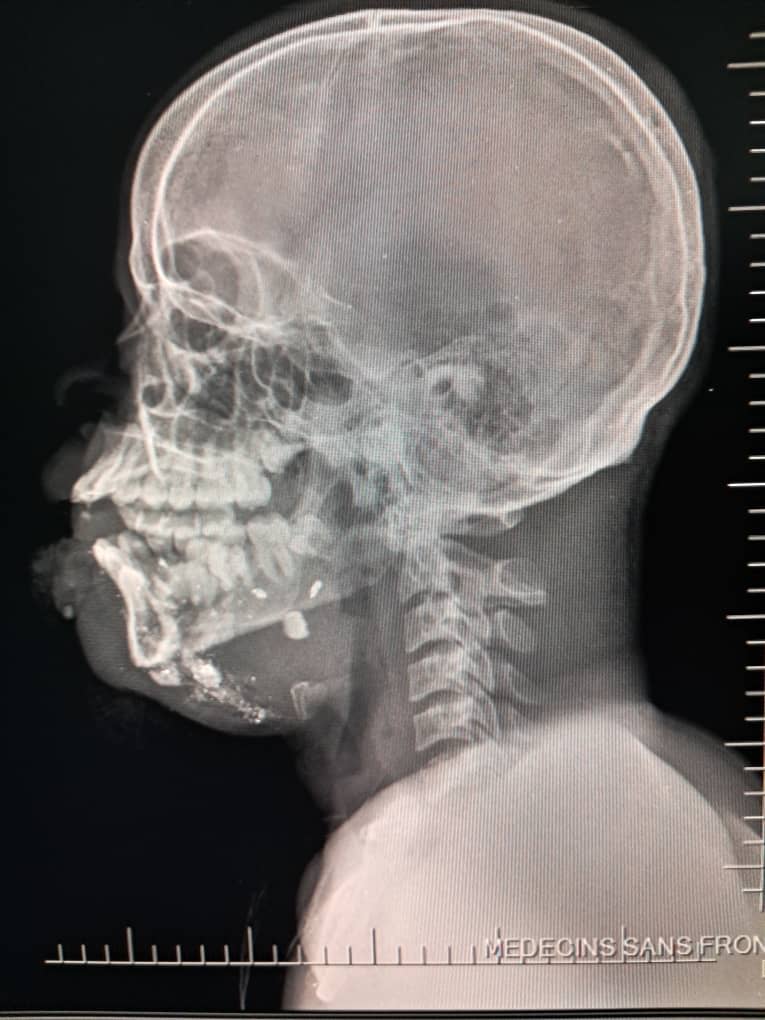

En los primeros seis meses de 2025, los equipos de MSF atendieron a 2.600 supervivientes de violencia sexual, ingresaron a 13.300 pacientes en urgencias y trataron a 2.267 víctimas de violencia. De estas últimas, el 26 % eran menores de edad, frente al 11 % en 2024. La mayoría de los menores tenían menos de 15 años y un tercio eran niñas. En este periodo, uno de cada tres menores ingresados por lesiones relacionadas con la violencia sufría heridas de bala.

El 20 de septiembre, 17 heridos fueron atendidos en el hospital de MSF en Drouillard tras un ataque con drones llevado a cabo ese mismo día en el barrio de Cité Soleil. Entre estos pacientes se encontraban dos hombres que ya habían fallecido a su llegada, otro hombre que murió durante el traslado, diez mujeres —una de ellas murió de camino al Hospital de traumatología de MSF en Tabarre— y tres niños que, trágicamente, no sobrevivieron a sus heridas. Otras dos mujeres heridas en el mismo ataque fallecieron en el cercano Hospital materno Isaïe Jeanty, donde también trabaja MSF.